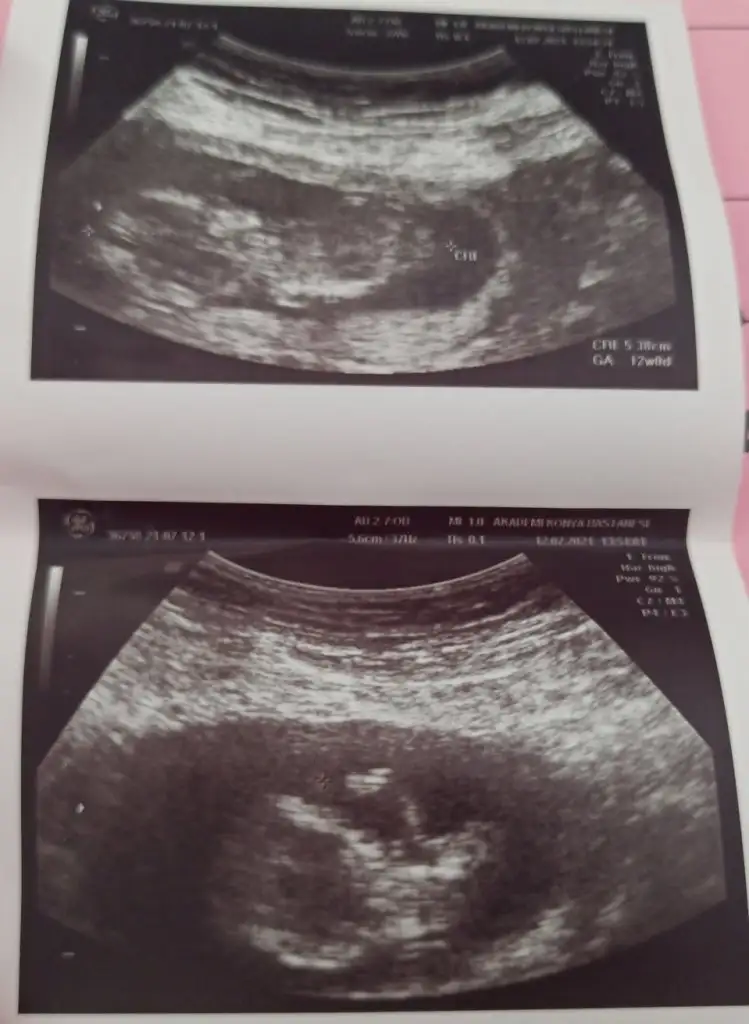

12+3 de gittim ben 7 küsürdü crl si işteyim ultrason kağıdı yanımda değil küsüratını hatırlamıyorum onun için ama doktorun dediği biri tam 1 hafta diğeri 5 gün büyük haftasından 13+3 öndeki bebek 13+1 arkadaki bebek görünüyordu